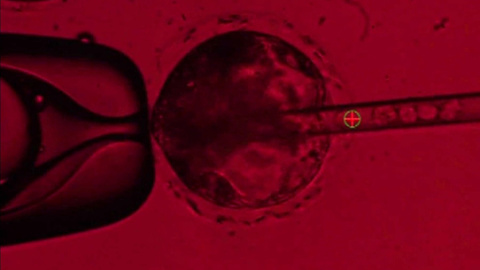

Para el desarrollo de embriones 'quimera', los científicos han recurrido al método de edición del genoma conocido como CRISPR para sacar ADN de un embrión porcino que ha sido fertilizado, lo que crea un "vacío" genético y permite entonces inyectar en él células madre humanas pluripotentes, indica la BBC.

El equipo, encabezado por Pablo Ross, confía en que las células madre humanas aprovechen el vacío genético en el embrión porcino para que el feto pueda desarrollar un páncreas humano.